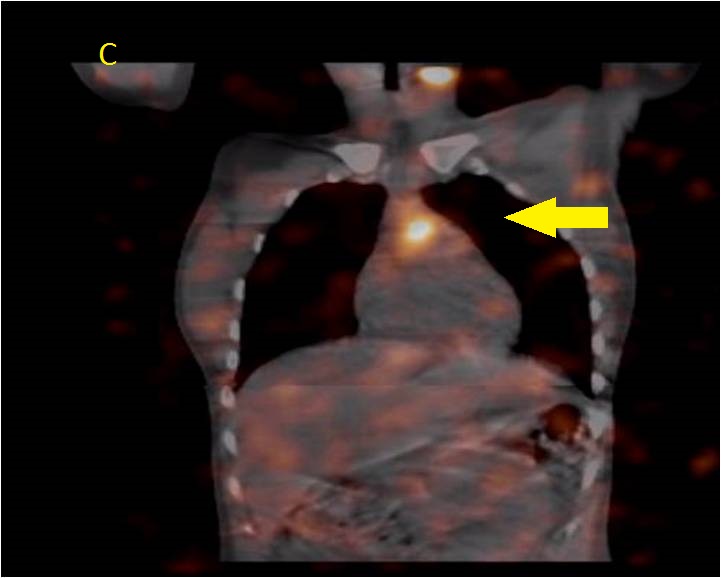

Female 24 y/o underwent total thyroidectomy on april 7th 2016, biopsy confirmed localized papillary oncocitic carcinoma. She was started on 125 ug of thyroxine per day. On june 8th 2016, 3.7 GBq were administered orally after using im Thyrogen 0.9 mg 48 h and 24 h before the radioiodine.

Anterior neck (A) and thoracic (B) views show 3 foci of I-131 uptake probably due to remnant tissue in the thyroid bed (black arrow). Note, Mid Thoracic irregulas uptake, less intense. Spect-CT fusion imagesĀ in (C) and (D) slices, depict anterior localization of the tracer, corresponding to Thymus (yellow arrow).